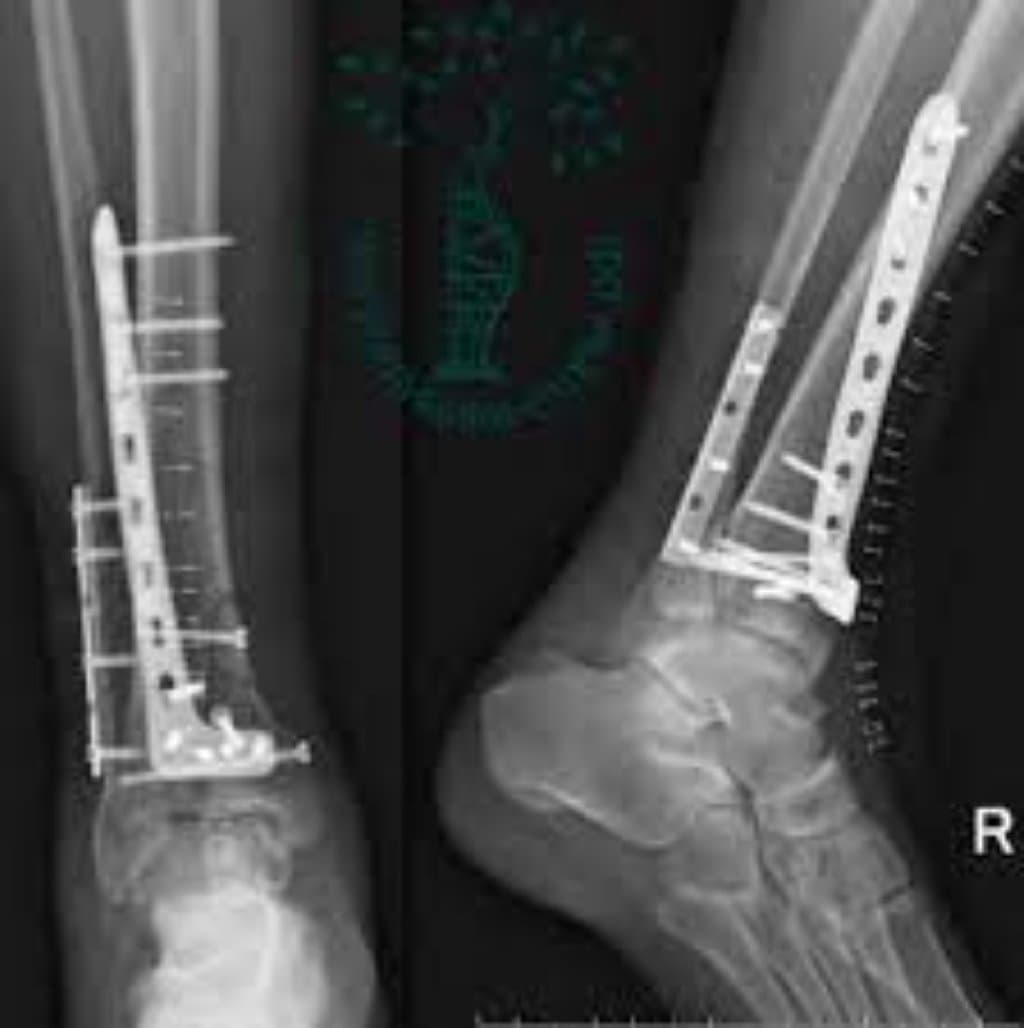

Plitə və Vida Osteosintezi: Bu, ən çox yayılmış osteosintez üsullarından biridir. Sınıq sümük parçaları bir-birinə sıx şəkildə düzülür və metal lövhə və vintlər istifadə edərək sabitlənir. Plitə sınıq sahəsinin üzərinə qoyulur və vida qırılan parçaları bir-birinə bağlamaq və sağalma prosesinə kömək etmək üçün boşqab və sümüyü təmin edir. Bu üsul uzun sümüklərdə (məsələn, bud və ya humerus) və qısa sümüklərdə (radius və ya dirsək sümüyü kimi) istifadə edilə bilər.

Sümük lövhəsinin osteosintezi: Bu üsul metal və ya titan kimi materiallardan hazırlanmış xüsusi sümük lövhələrinin istifadəsini nəzərdə tutur. Sümük lövhələri qırılan sümük parçalarına qoyulur və vintlər və ya boltlar vasitəsilə sümük parçalarına bərkidilir. Sınıqların daha böyük və ya daha mürəkkəb olduğu hallarda bu üsula üstünlük verilir.